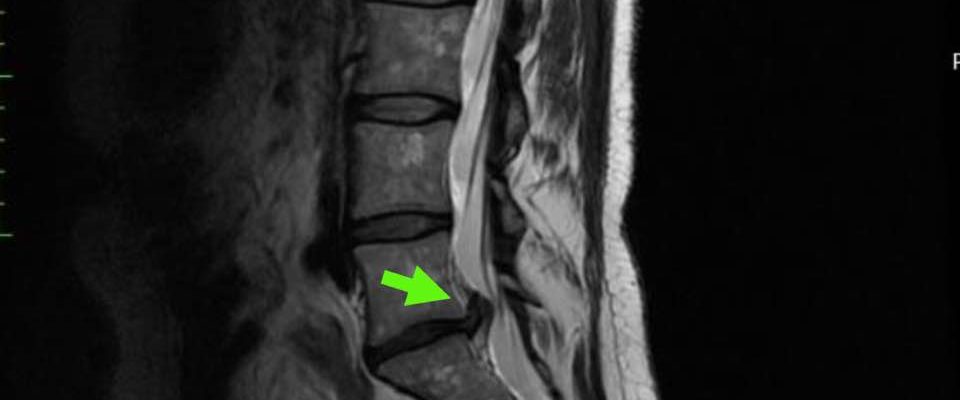

L5S1腰椎間盤突出